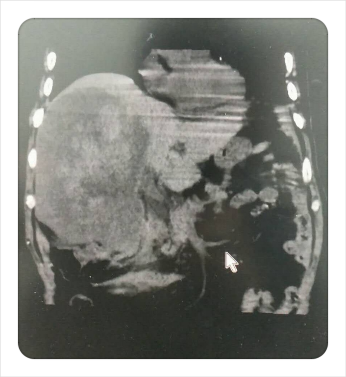

同时,在医技护及家属的协同下,通过放射科绿色通道患者在短时间内完善了腹部急诊CT检查,结果显示:右肝巨块型肝癌破裂出血伴腹腔积血。迅速完善术前评估,告知家属患者病情危重需行急诊介入手术,家属表示同意并签署手术同意书,随即推入DSA手术室。闻讯赶来的放射介入团队接过病人后在梁琪主治医师的带领下迅速行经导管肝动脉造影+栓塞术。术中造影证实患者右肝VI段区域一破裂出血肝动脉分支,立刻行微导管插管,予以PVA颗粒超选择性栓塞,再次造影后右肝VI段出血动脉未见明显显影,且未见异位栓塞征象。术后患者生命体征平稳,安返病房。